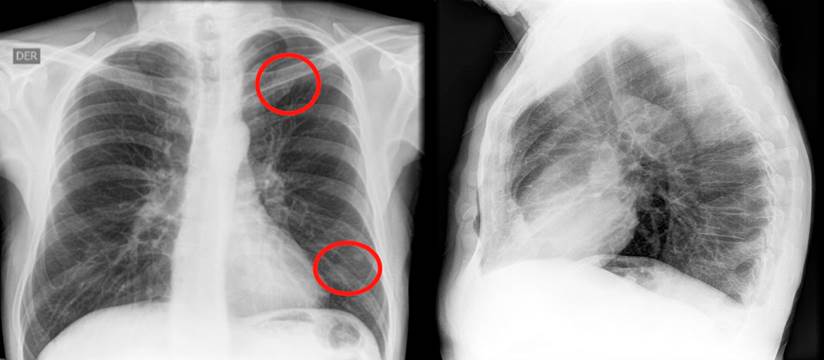

During an endoscopic check-up, ulcerative pancolitis and pseudopolyps were found, which, compared with the previous colonoscopy, showed a progression of the disease, thus the initiation of biological therapy was considered. Tests for tuberculin (purified protein derivative, PPD), hepatitis A, B, and C, and HIV were performed. A chest x-ray was also done, revealing a nodule in the left upper lobe and a nodule in the lower lobe, 6 mm each (Figure 1). A computed tomography of the chest confirmed these findings (Figure 2).

Figure 1 Nodular opacification with soft tissue density in the upper and lower left lobes on the chest x-ray. Source: Own elaboration.